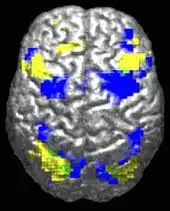

Altered circuit connectivity

The underconnectivity theory of autism posits that autistic people tend to have fewer high-level neural connections and less global synchronization, along with an excess of low-level processes.[27] Functional connectivity studies have found both hypo- and hyperconnectivity in brains of autistic people.[28] Hypoconnectivity is commonly observed for interhemispheric and cortico-cortical functional connectivity.[29] Some studies have found local overconnectivity in the cerebral cortex and weak functional connections between the frontal lobe and the rest of the cortex.[30] Abnormal default mode network (task-negative) connectivity is often observed. Toggling between task-negative network activation and task-positive network activation (consisting of the dorsal attention network and salience network) may be less efficient, possibly reflecting a disturbance of self-referential thought.[31] Such patterns of low function and aberrant activation in the brain may depend on whether the brain is performing social or nonsocial tasks.[32]